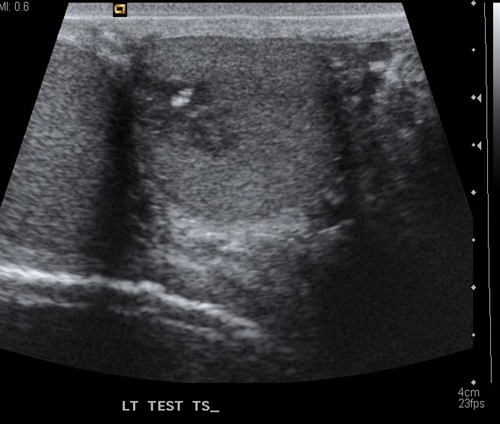

Figure 2.US of teratoma seen as a low echo lesion containing an area of central calcification.

Seminomas can have a uniform appearance and are generally of low echogenicity but larger tumours may be heterogenous and lobulated (Figure 1). Typically, teratomas are described with areas of calcification and are heterogenous, also containing fluid. They can have areas of central necrosis and haemorrhage (Figure 2). Both tumours are classically hypervascular, but depending on areas of fluid or necrosis may be hypovascular. Lymphoma tends to be infiltrative involving the whole testis and causing diffuse testicular enlargement rather than a more focal tumour.